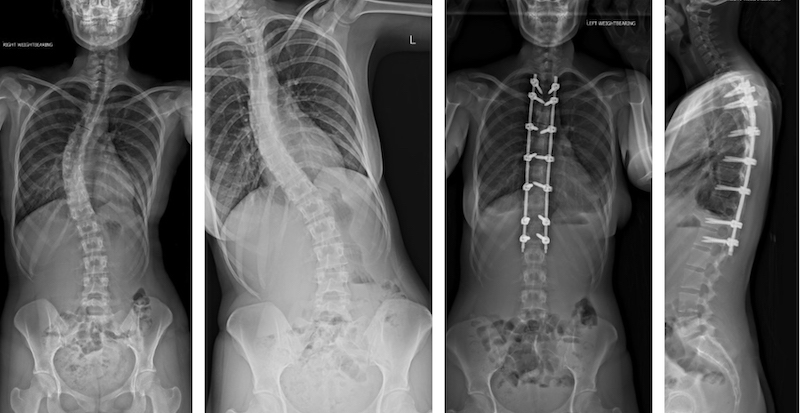

Camille was diagnosed with scoliosis in 2017, and surgery to correct the 40-degree curvature in her spine was booked for the start of 2020. But Covid put the brakes on that plan, and she was unable to have the operation until February – just months before her final project had to be completed.

X-rays of Camille's own spine, pre- and post-surgery provided the inspiration for her designs